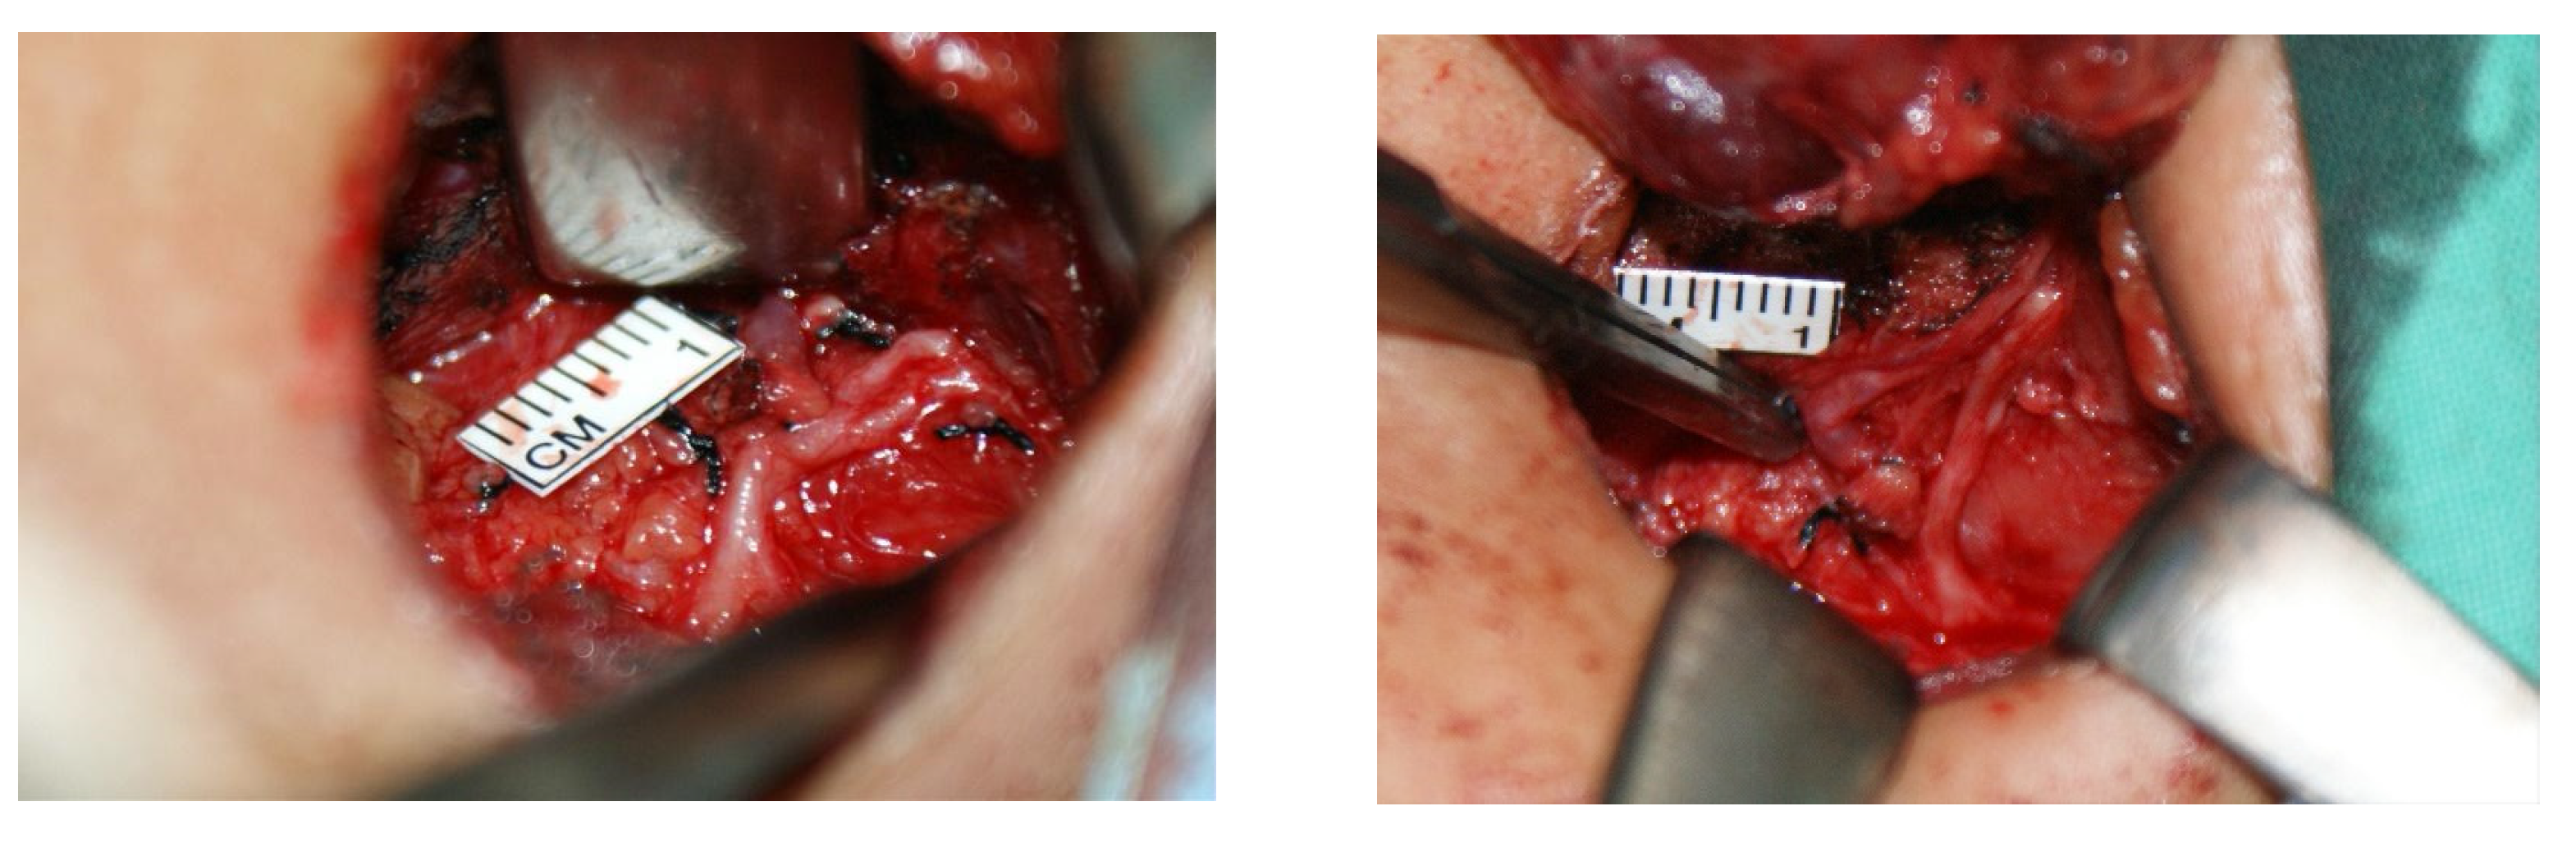

Figure 2. Left non-recurrent laryngeal nerve found during left thyroidectomy, arising from the vagus nerve at the level of the thyroid toward the trachea.